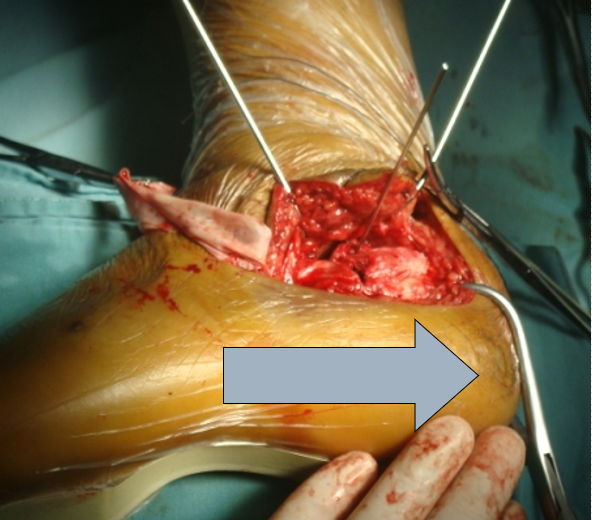

手术刀要一刀见骨,将骨膜连同软组织以及腓骨长短肌肌腱一起向上掀起。

切开皮肤后开始用7号丝线协助牵开

技巧三、克氏针的位置剥离骨膜后,3根克氏针牵开皮肤。注意距骨前后一根,骰骨一根。这样显露充分

骨刀将跟骨外侧壁翻开,同时跟骨内翻即可清晰显露距下关节和跟骨后关节面